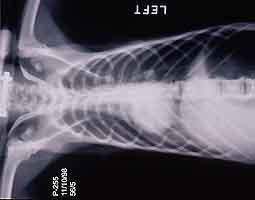

- Case 23-3. The A/P thoracic radiograph shows marked

right sided deviation of the cardiac silouette. The lateral thoracic

- Thoracic radiographs demonstrated an increased pulmonary

interstitial pattern with air bronchograms bilaterally. The cardiac

silhouette was shifted to the right. Abdominal radiographs demonstrated